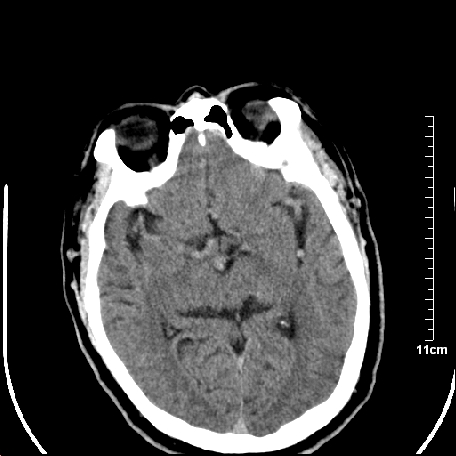

外伤患者,什么病,

外伤患者,没什么症状,

双侧外侧裂,左侧脑沟见高密度结节影,边清,还有鞍上池层面密度也高

都是血管。

脑血管硬化?高血红蛋白症?

1.左额叶脑软化灶。

2.老年脑,基底动脉硬化迂曲。

基底动脉硬化迂曲。高血红蛋白血症。